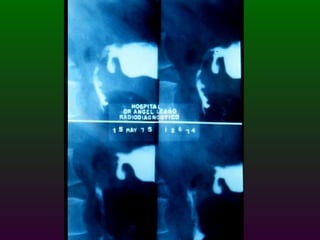

S.E.G.D.  Serie esófago gastro duodenal Definición  Estudio de doble contraste (bario) y aire del tracto digestivo superior. (esófago, estómago, duodeno)

SEGD La impresión radiológica básicamente se divide en tres limitados y un difuso Ulceración Estrechez Masa Compromiso difuso por ulceración y/o engrosamiento  parietal

SEGD PATOLOGÍA  ESOFÁGICA A.- Estrechamientos y dilataciones secundarias Acalasia Estenosis Esclerodermia Enf. de Chagas Neoplasia Lesiones por quemadura (cáusticos y dietéticos etc.)